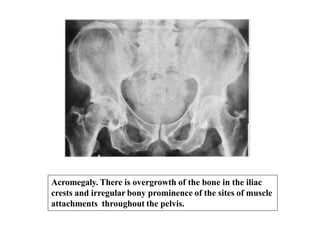

Acromegaly. There is overgrowth of the bone in the iliac

crests and irregular bony prominence of the sites of muscle

attachments throughout the pelvis.